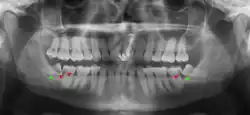

Las muelas del juicio retenidas se clasifican por la dirección de impactación, su profundidad en comparación con la superficie de mordida de los dientes adyacentes y la parte de la corona del diente que atraviesa el tejido gingival o el hueso. Las muelas del juicio impactadas también pueden clasificarse por la presencia o ausencia de síntomas y enfermedad. La detección de la presencia de muelas del juicio suele comenzar al final de la adolescencia, cuando una muela parcialmente desarrollada puede quedar retenida. La exploración suele incluir un examen clínico y radiografías panorámicas.

Si el diente no se puede evaluar únicamente con el examen clínico, el diagnóstico se realiza mediante una radiografía panorámica o una tomografía computarizada de haz cónico. Cuando las muelas del juicio no erupcionadas todavía tienen potencial de erupción, se utilizan varios factores predictivos para determinar la probabilidad de que los dientes se impacten. La relación de espacio entre la longitud de la corona del diente y la cantidad de espacio disponible, el ángulo de los dientes en comparación con los otros dientes son los dos predictores más utilizados, siendo la relación de espacio la más precisa. A pesar de la capacidad de movimiento en la edad adulta temprana, la probabilidad de que el diente se impacte puede predecirse cuando la relación entre el espacio disponible y la longitud de la corona del diente es inferior a 1.:[5] 141

No existe una norma para detectar las muelas del juicio. Se ha sugerido, a falta de pruebas que apoyen la retención o extracción rutinaria de las muelas del juicio, que la evaluación con radiografía panorámica, comenzando entre los 16 y los 25 años de edad, se realice cada 3 años. Una vez que exista la posibilidad de que los dientes desarrollen una enfermedad, se recomienda una discusión sobre los riesgos operativos frente al riesgo a largo plazo de la retención con un cirujano oral y maxilofacial u otro clínico capacitado para evaluar las muelas del juicio. Estas recomendaciones se basan en pruebas de nivel de opinión de expertos.[19] Puede ser necesaria la exploración a una edad más temprana si los segundos molares (los "molares de los 12 años") no erupcionan, ya que la posición ectópica de las muelas del juicio puede impedir su erupción. Las radiografías pueden evitarse si la mayor parte del diente es visible en la boca.